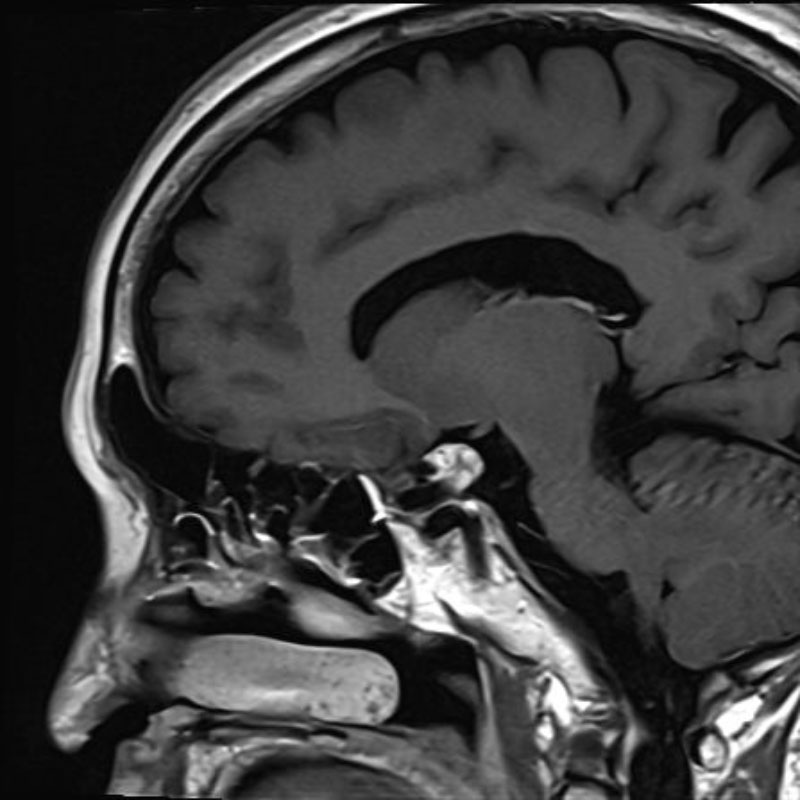

断層撮影

手術前1